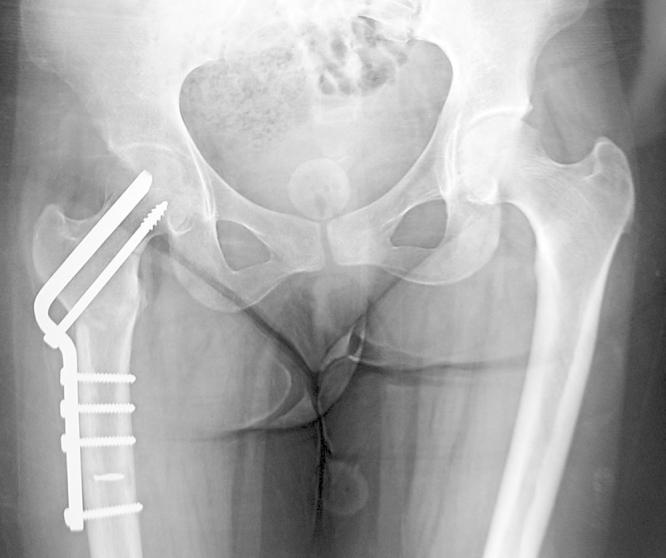

Osteomalacia and coxa vara. An unusual co-existence for femoral neck stress fracture.

Femoral neck stress fractures are not uncommon. Several causes exist about these fractures. Osteomalacia is one of the most common cause of insufficiency fractures and coxa vara can produce a focal concentration of mechanical stress in the femoral neck and may cause stress fractures. This case study is about the co-existence of these two pathologies in a patient with bilateral femoral neck stress fracture.

A 26-year-old woman admitted to our department with a complaint of bilateral groin pain and diagnosed as bilateral coxa vara and osteomalacia. Medical treatment for osteomalacia and staged bilateral Pauwels' osteotomy was performed. After 2 years of follow-up, good result was obtained.

There are several risk factors for stress fractures and osteomalacia and coxa vara are two of the causes. Osteomalacia results in softening of the bones and coxa vara can produce a focal concentration of stresses in the femoral neck.